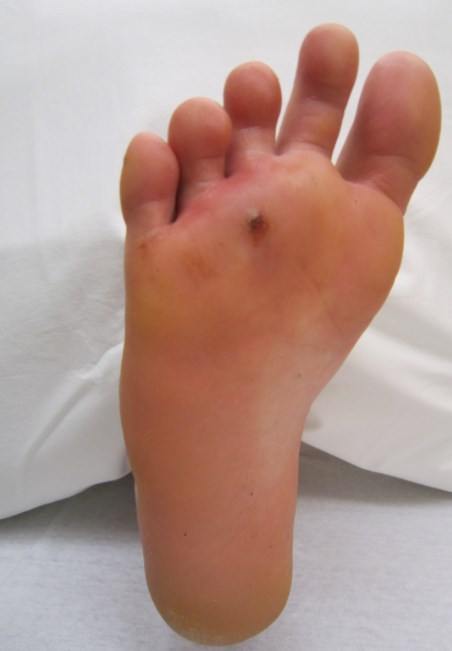

• Table 4 summarizes common characteristics of neuropathic (Figure 8), ischemic (Figure 9) and neuroischemic ulcers (Figure 10) in DFU [8][10][9] [83][84][85].

Table 4. Typical characteristics of DFU according to etiology (adapted from Chadwick) [8][10][9][83][84][85]

Figure 8. Neuropathic ulcer in the heel of a 68-year old patient with diabetes [86]

Prevalence [10]

35%

Anatomic location

Neuropathic ulcers usually occur on areas that bear weight and/or are subject to abnormal pressure/shear. Common areas are the plantar aspect of the foot under the metatarsal heads or on the plantar aspects of the toes [8][82][83], heel and over the dorsum of claw or hammer toes [8][82][83].

Sensation

Sensory loss

Foot temperature

Warm

Foot pulses

Present

Callus

Present, often thick

Shape

Surrounding callus, even round margins

Wound bed

Pink and granulating, surrounded by callus. Necrotic base uncommon, low-to-moderate drainage

Pain intensity

Mild

Type of pain

Neuropathic (sharp, stabbing or burning) pain may be present